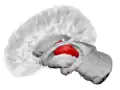

Thalamus

360 rotation of Thalamus

The thalamus in a 360° rotation